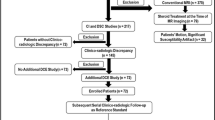

MR PW imaging

a PWI pattern analysis (N = 25) and b PWI subanalysis (N = 13) showing high or low rCBV at baseline and during follow-up. Numbers of metastases evaluated at each time point are added as well as the number of patients with PsPD, non-PD, PU and PD in case it is their last follow-up moment. Red colour high rCBV, blue colour low rCBV, PWI perfusion weighted image, FU follow-up, PsPD pseudoprogression, non-PD no progressive disease, PU progression unspecified (progressive disease or pseudoprogression), PD progressive disease

The subanalysis contained only the metastases with a definite outcome; PsPD, PD and non-PD. A total of 13 metastases were included. In 12/13 (92%) the follow-up PWI demonstrated a concordant result with the changes in the estimated area of contrast enhancement; low rCBV in case of PSPD or non-PD and high rCBV in case of PD (Fig. 1b). However, one metastasis categorized as non-PD demonstrated a high rCBV at baseline and at 3 and 6 months of follow-up.